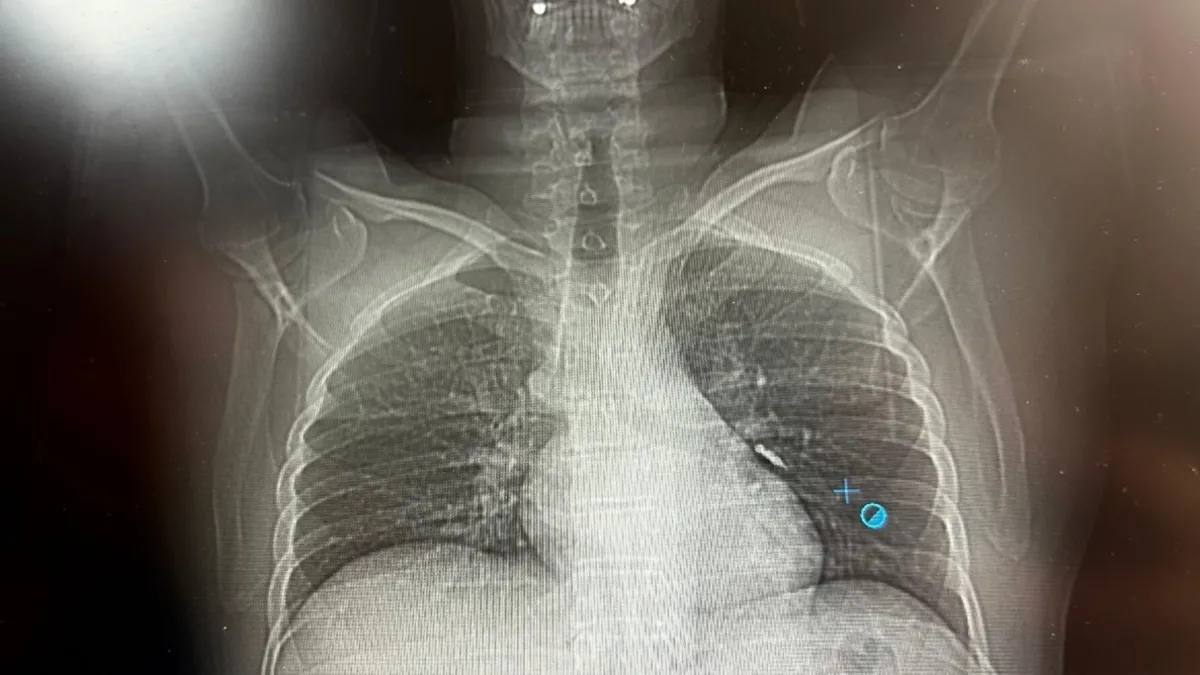

Konuya ilişkin konuşan Göğüs Cerrahi Op. Dr. Sadullah Aksoy, bir diş merkezinde diş tedavisi sırasında hastanın çenesine yerleştirilen implantın vida kısmının işlem esnasında yanlışlıkla aspire edildiğini belirtti. İlk olarak hastanenin ek hizmet binasında çekilen tomografi sonucunda, vidanın sol akciğerin hava yollarının yaklaşık dördüncü dalına kadar ilerlediği tespit edildiğini ifade eden Op. Dr. Aksoy, "Geçtiğimiz cumartesi günü öğle saatlerinde tarafımıza ulaşıldığında, hastanın Van Eğitim ve Araştırma Hastanesi'ne yönlendirilmesini istedik. Burada acil bronkoskopi planı yapılarak hasta kabul edildi. Hasta geldiğinde genel durumu iyiydi; solunumunu tamamen engelleyen bir bronş tıkanıklığı söz konusu değildi. Aynı gün hastamızı hazırladık. Bronkoskopi sırasında, implant vidasının sol üst lobun anterior segment bronşuna saplanmış pozisyonda olduğunu gördük. Üroloji bölümünde taş çıkarma işlemlerinde kullanılan cihazla müdahale ettik. İlk denemede implant tamamen çıkarılamadı ancak yerinden oynatılabildi. Bunun üzerine bir süre bekleyip hastayı yeniden bronkoskopi için hazırlamaya başladık. İşlem yaklaşık 3,5-4 saat sürdü ve saat 18.30 civarında hasta işlemden çıkarıldı" dedi.

Daha sonra hasta için yeniden bronkoskopi planladıklarını ancak bu süreçte hasta şiddetli bir öksürük geçirdiğini anlatan Aksoy, "Şiddetli öksürük sonrası yapılan kontrol akciğer filminde implant vidası görünmedi. Bunun üzerine toraks ve batın BT (bilgisayarlı tomografi) görüntülemesi istedik. Sonuçlarda implantın akciğerden çıktığı ve vücutta herhangi bir yerde bulunmadığı tespit edildi" diye konuştu.